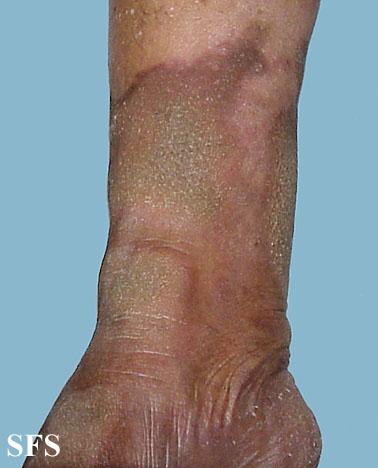

progressive palmoplantar keratoderma